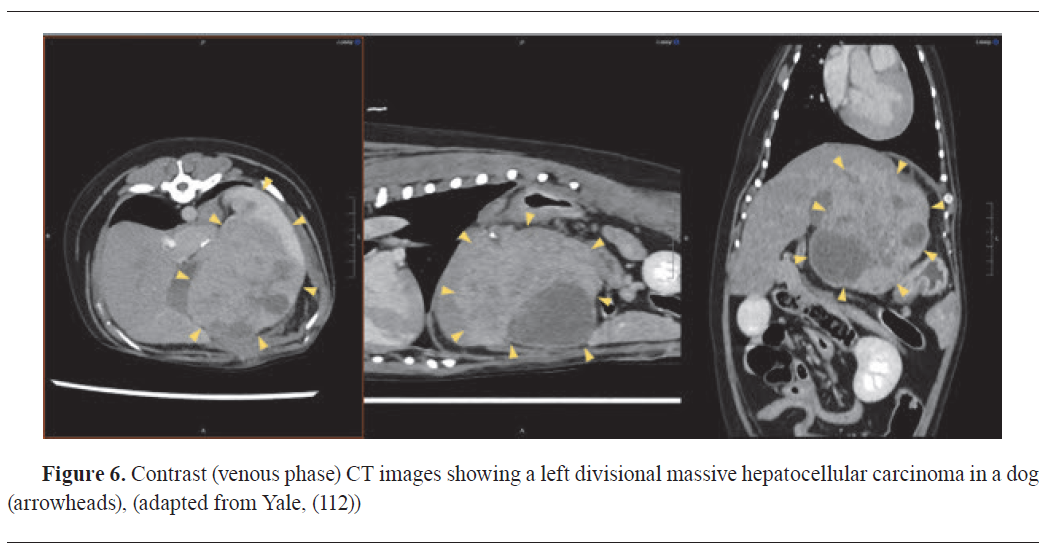

DIAGNOSTIC USES OF ULTRASONOGRAPHY IN VETERINARY ONCOLOGYDiagnostic ultrasound utilizes ultrasound waves to make image of internal organs tumours (

Fig. 5). It is based on the reflection of sound waves from the border between two tissues with different acoustic impedances. The acoustic impedance of targeted tissues depends on its physical density and the achievable velocity of the sound waves sent from the transducer into the tissue (

59,

61). In veterinary clinical practice, contrast-enhanced ultrasonography allowed the precise assessment of visceral organ vascularization in healthy dogs and the differentiation between malignant and benign visceral organ nodules in dogs and cats based on perfusion patterns (

Fig. 5) (

70). Compared with the other diagnostic imaging techniques, ultrasonography has the advantages of fast real-time imaging, low cost, and the lack of x-ray exposure. Disadvantages are limited imaging of the bone and air-filled spaces, comparably low image resolution, and a limited body penetration (

61).